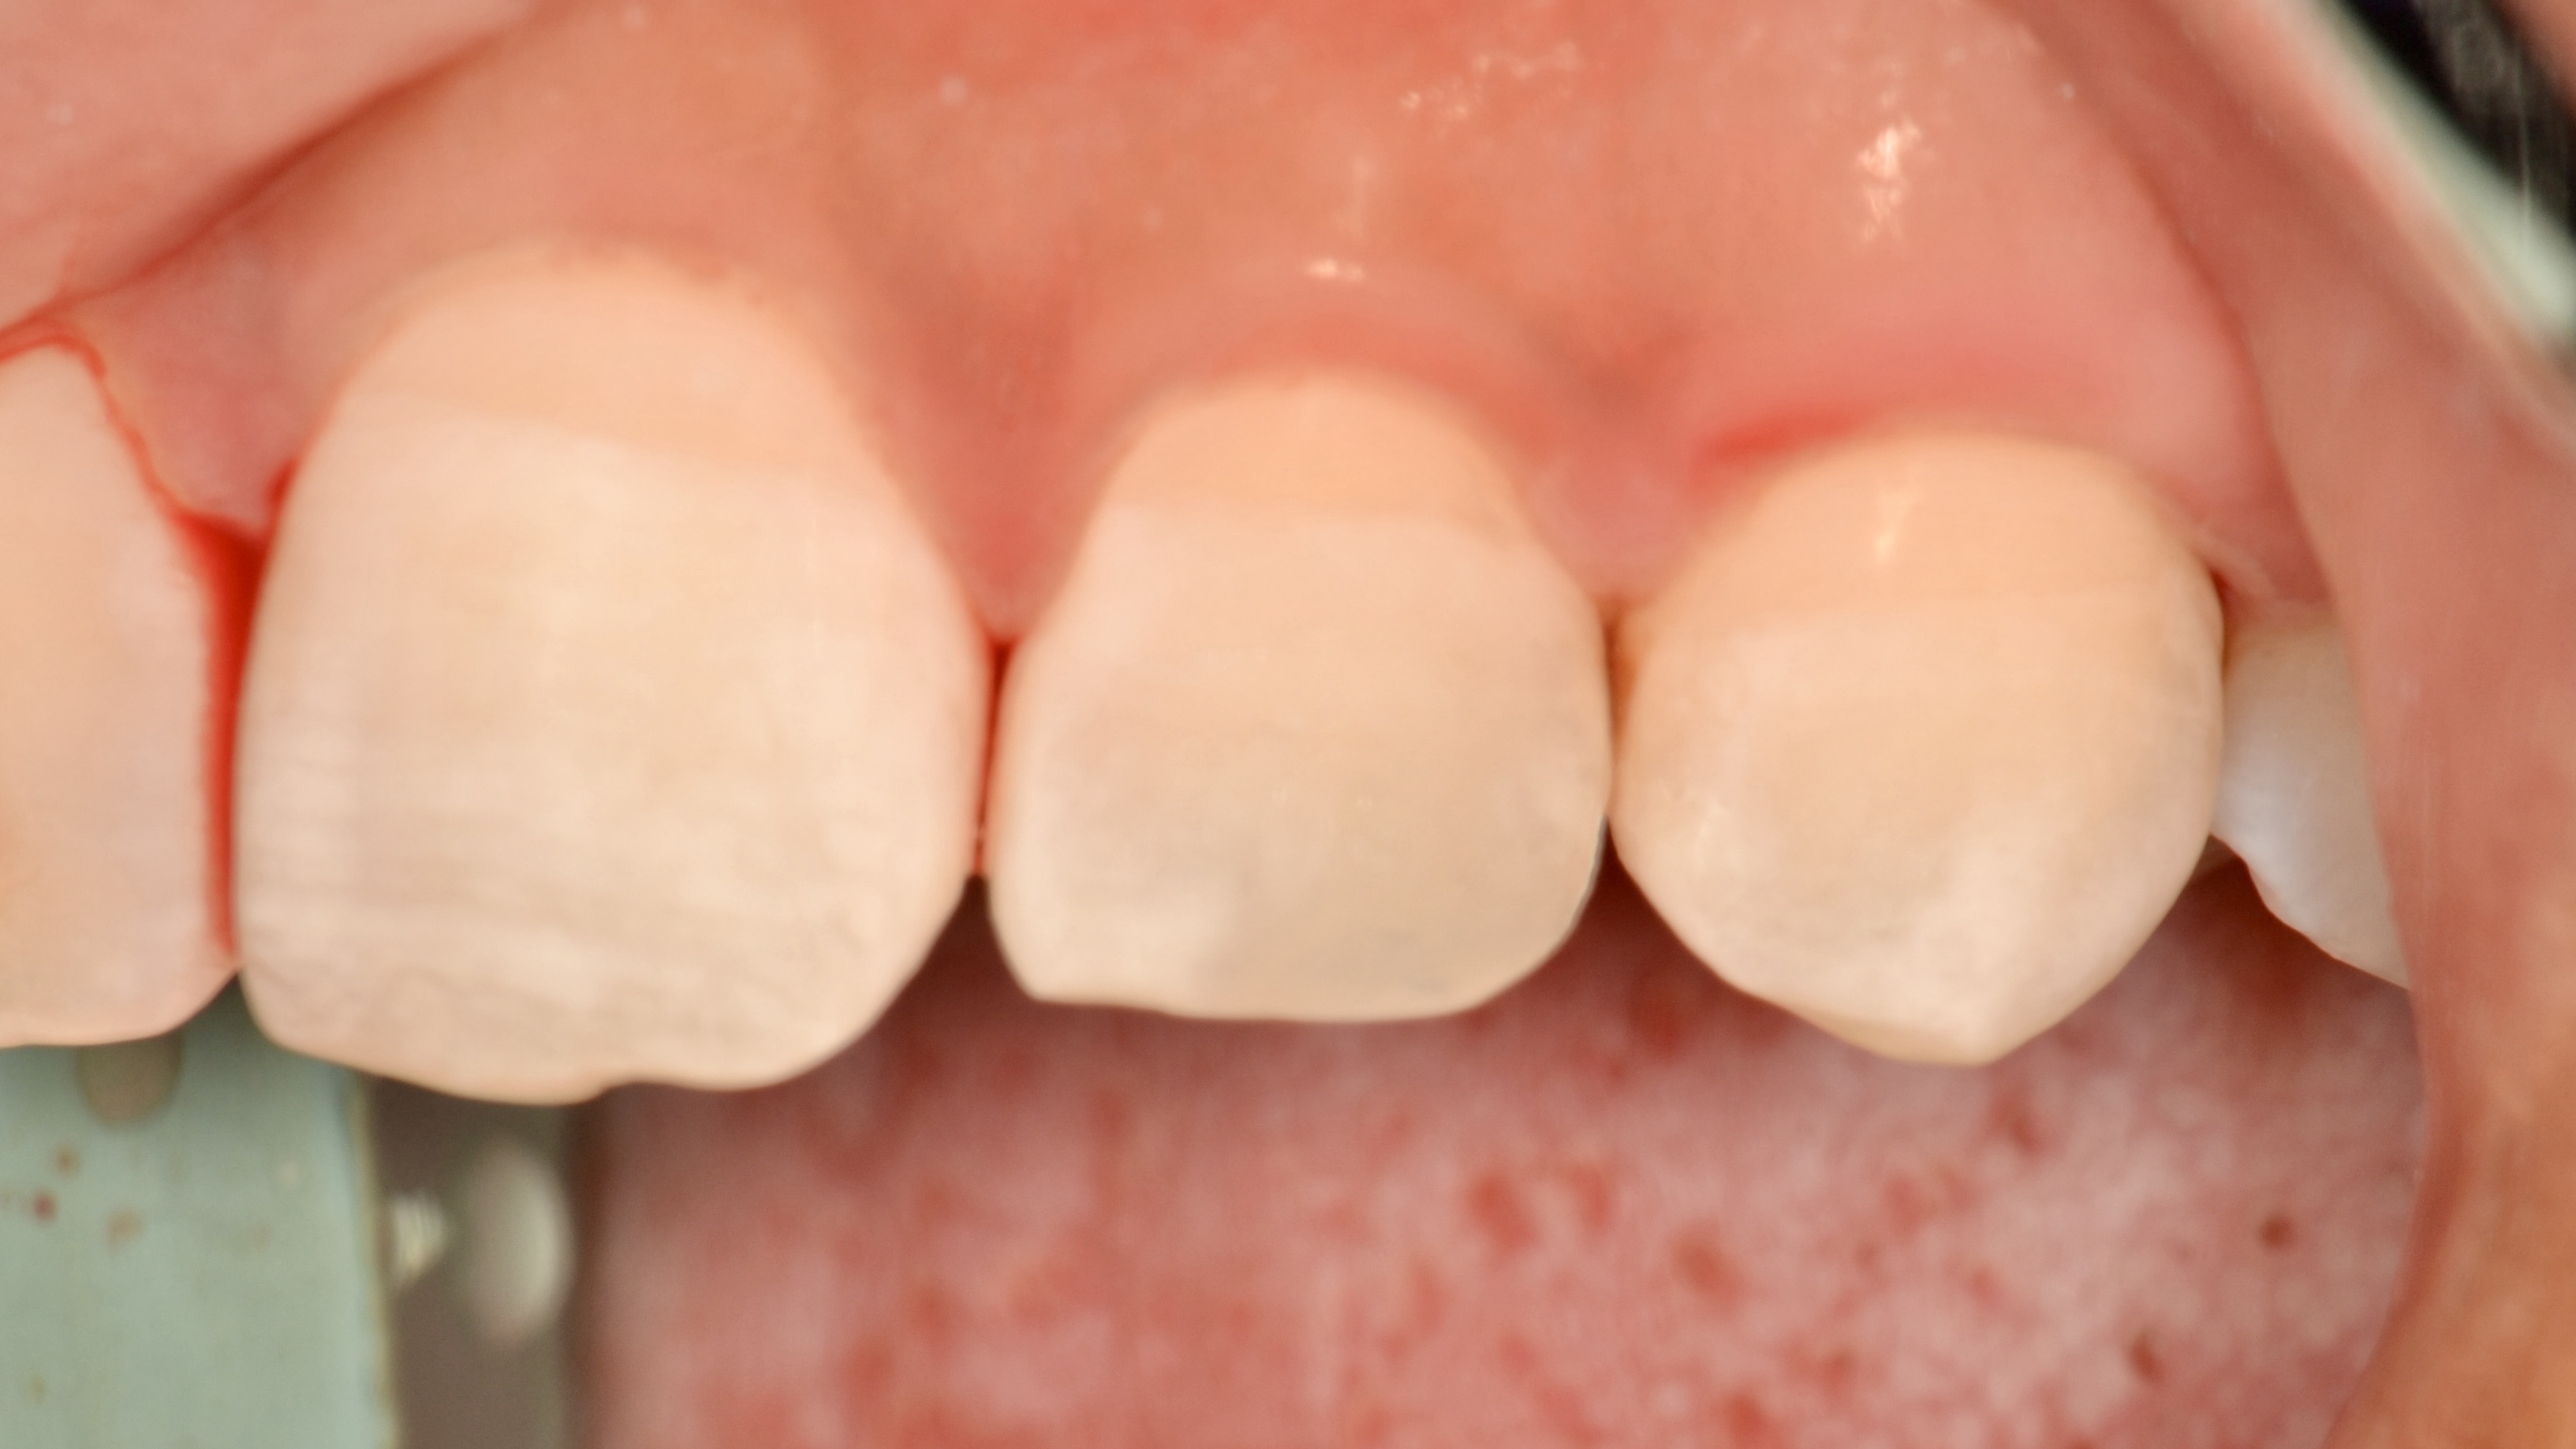

Custom Ceramic Crowns